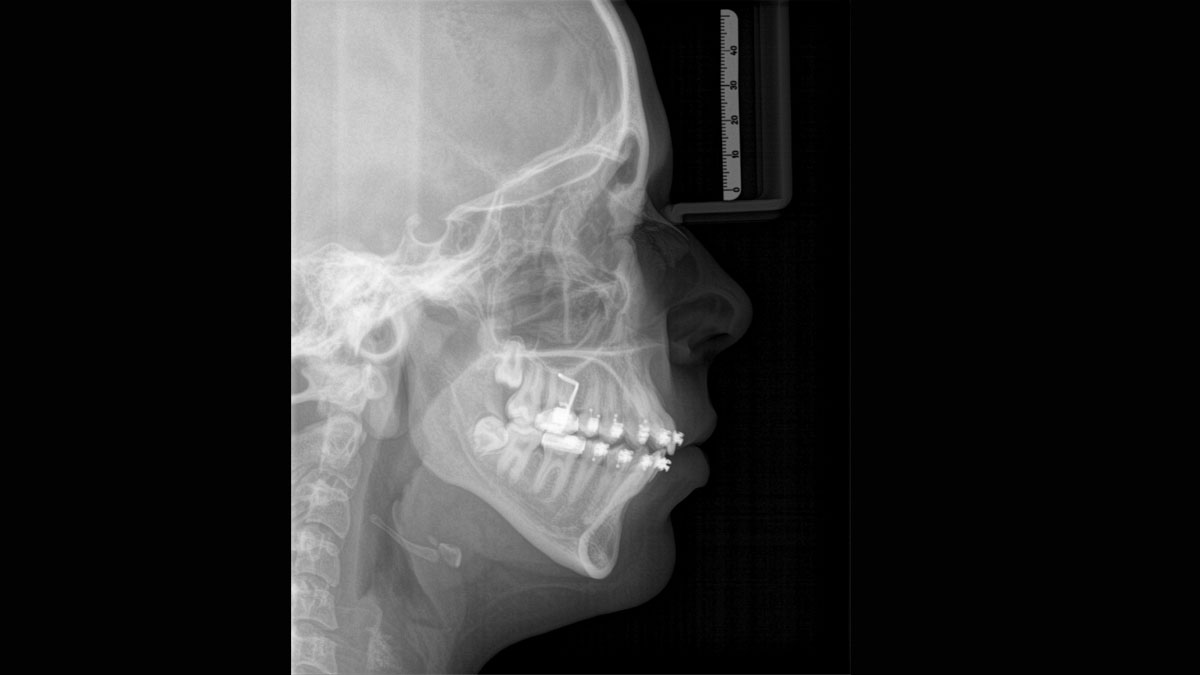

Para obtener imágenes panorámicas excepcionales con alta nitidez. Puede elegir un brazo cefalométrico derecho o izquierdo opcional, que puede reacondicionarse en cualquier momento

El sensor de conversión directa (Direct Conversion Sensor, DCS) ha revolucionado el estándar de la imagen panorámica. Las imágenes radiológicas se convierten directamente en señales eléctricas. Por lo tanto, no hay pérdida de señal debido a conversión de la luz, como es el caso de los sistemas convencionales. El resultado: imágenes con un alto nivel de nitidez y contraste, incluso con una dosis de radiación extremadamente baja. Para obtener información de diagnóstico precisa a fin de apoyar el tratamiento objetivo.

La imagen a continuación muestra una radiografía panorámica con y sin tecnología DCS. Usando la flecha, arrastre el control a través de la imagen para ver la diferencia que el sensor de conversión directa hace con la calidad de la imagen y las posibilidades de diagnóstico.

El enfoque correcto es crucial para excelentes radiografías panorámicas. Con la función de autofoco, usted recibirá automáticamente una imagen con la mejor nitidez posible en foco. Los dispositivos de radiología de Dentsply Sirona toman varios miles de imágenes individuales en un ciclo e identifican automáticamente las áreas donde la mandíbula está posicionada de manera óptima. Luego, sin ningún paso manual adicional, estas imágenes se muestran en una nítida imagen final.